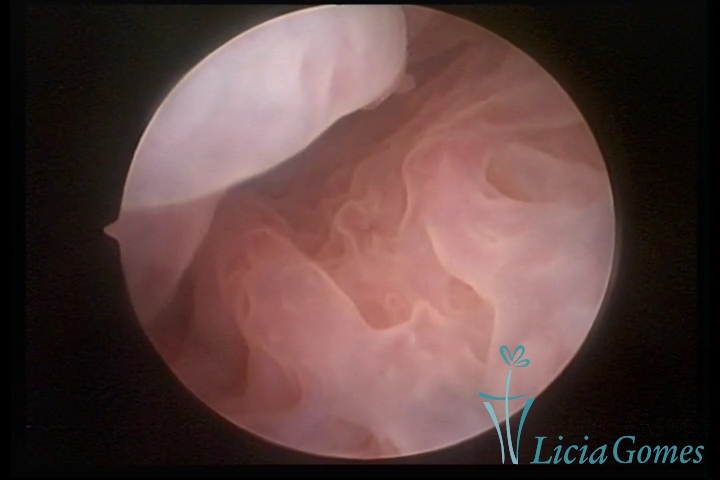

First part or proximal section or lower section:

During the proliferative phase, a light, crystalline mucus with a low adherence to the scope is found. The crypts and buds are a little swelled and vascularized, microvesicular, resembling grape clusters.